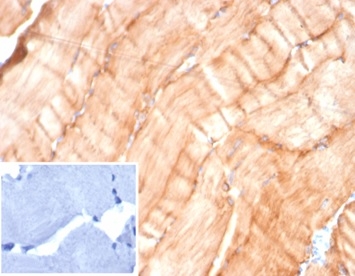

Formalin-fixed, paraffin-embedded human skeletal muscle stained with Desmin Mouse Monoclonal Antibody (DES/4526) at 2ug/ml. Inset: PBS instead of primary antibody; secondary only negative control.